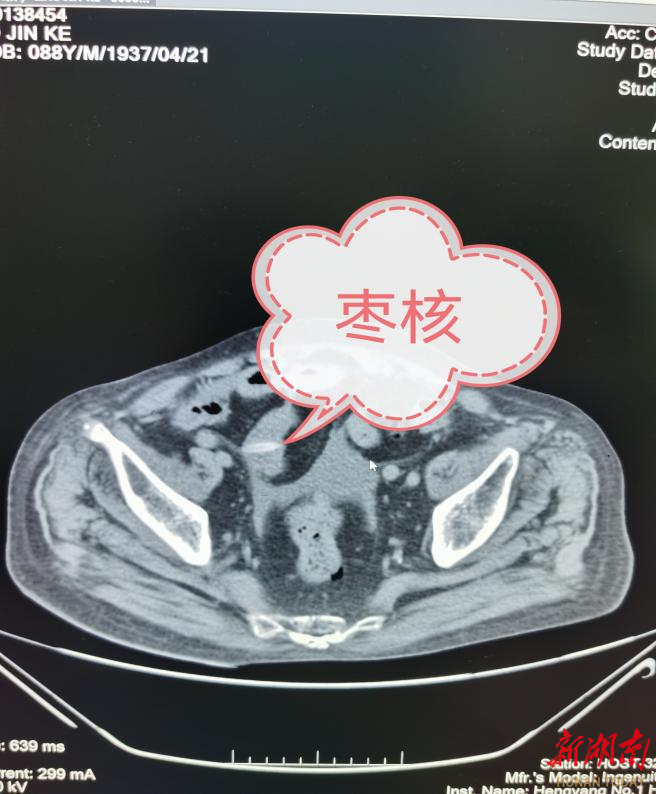

事发当日,廖爷爷食用红枣时不慎囫囵吞下,随后出现剧烈腹痛。转至衡阳市第一人民医院普通外科时,患者已出现严重腹腔感染、全身性感染及感染性休克等症状,危在旦夕。科室主任吕海涛立即启动多学科联合会诊(MDT)机制,普通外科、重症医学科(ICU)、呼吸与危重症医学科、手术室、麻醉科等多学科专家迅速集结, 共同制定周密的治疗方案。在多学科无缝衔接配合下,手术团队为患者实施了急诊剖腹探查手术,成功取出异物并完成肠穿孔修补。